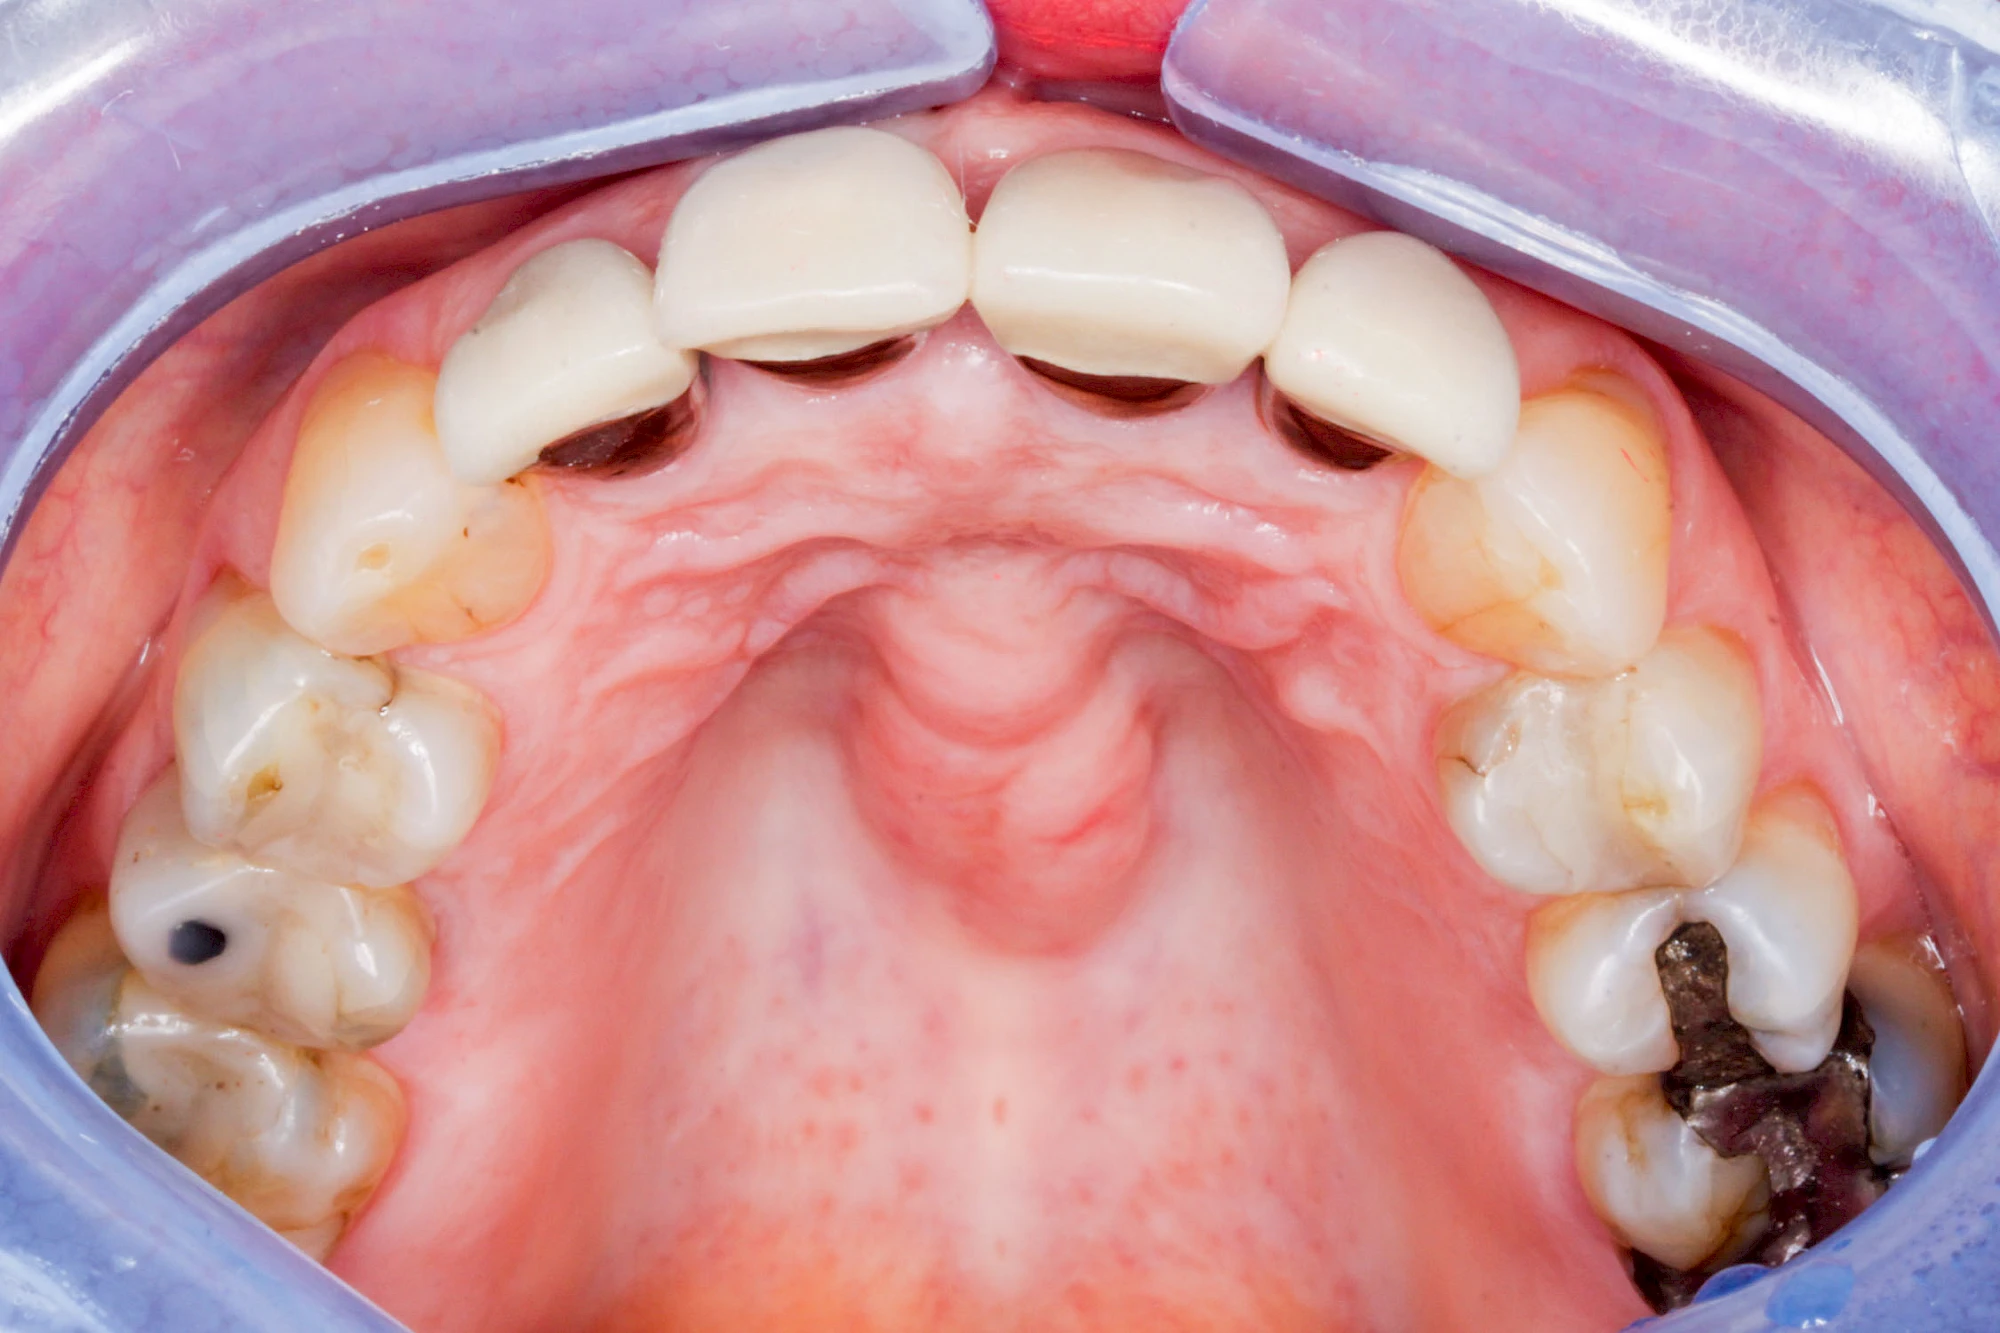

Überbein (Exostose)

Überbeine im Bereich der Kiefer sind gar nicht so selten. Häufiger im Bereich der Seitenzähne unterhalb des Zahnfleisches, aber auch in der Mitte vom Gaumen. Überbeine haben in dem Sinne keinen Krankheitswert, müssen also nicht operativ entfernt werden, wenn diese nicht stören. Überbeine können ein Anzeichen für Knirschen und Pressen sein.